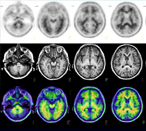

Clinical trials show brain PET imaging improves dementia diagnosis

Research reported at AAIC 2017 highlighted the clinical value of amyloid-β PET scans, which detect the presence of amyloid-beta plaques in the brain — one of the hallmarks of Alzheimer's disease. Studies also revealed an underutilization of amyloid-β PET imaging in clinical care, contributing to misdiagnosis of dementia. Learn more.